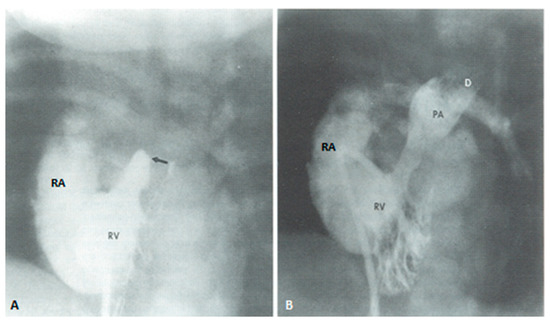

Following the initial description of subclavian artery-to-ipsilateral PA anastomosis (classic Blalock–Taussig (BT) shunt) in the mid-1940s [8], a number of palliative procedures to augment pulmonary blood flow have been devised over time and these include, descending aorta-to-left PA anastomosis (Potts shunt), ascending aorta-to-right PA anastomosis (Waterston-Cooley shunt), end-to-end superior vena cava-to-right PA anastomosis (classic Glenn shunt), enlargement of the VSD, formalin infiltration of the wall of ductus arteriosus, central aortopulmonary fenestration or expanded polytetrafluoroethylene (Gore-Tex; W. L. Gore & Associates, Inc, Newark, DE, USA) graft shunt, Gore-Tex interposition graft between the subclavian artery and the ipsilateral PA (modified BT shunt), balloon pulmonary valvuloplasty, bidirectional Glenn procedure and stent implantation into the ductus [9,10]. At the present time, most surgeons favor the modified BT shunt [11] using an interposition Gore-Tex graft between right or left subclavian artery to the ipsilateral PA (Figure 1).

If the predominant obstruction is at the pulmonary valve level, though uncommon, balloon pulmonary valvuloplasty [12,13] to increase the pulmonary blood flow may be performed; balloon pulmonary valvuloplasty apart from increasing pulmonary blood flow, promotes growth and development of the pulmonary artery (Figure 2) and left ventricle so that a total surgical corrective procedure could be performed safely at a later time [12,13,14,15,16].

In premature babies two different palliative procedures were used as a bridge to total correction later. Balloon pulmonary valvuloplasty has been used in premature babies with TOF and significant arterial desaturaion as a bridge to total correction [17]. Similarly, deployment of a stent in RV outflow tract (Figure 3) may be used to promote growth of the pulmonary arteries and facilitate complete surgical correction at a later time [18].